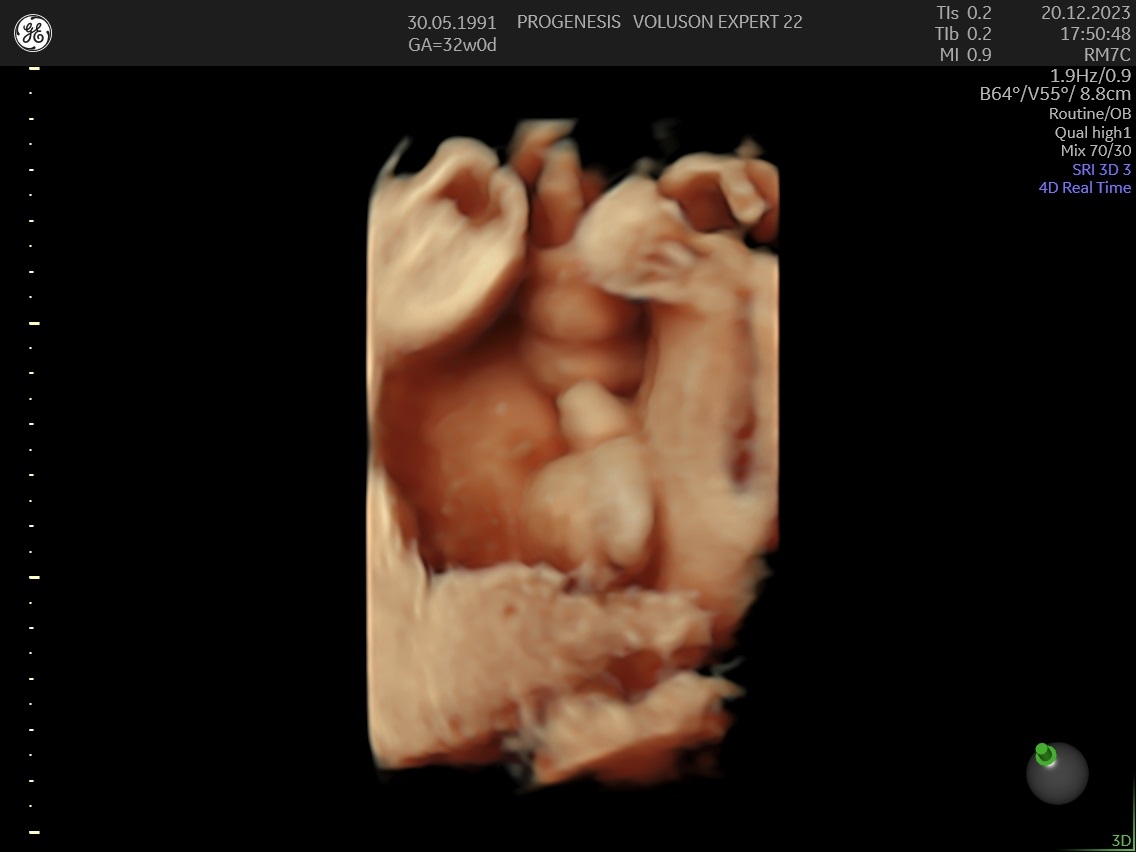

3D/4D LIVE Υπερηχογράφημα

Το 3D/4D LIVE είναι μια νέα τεχνολογία υπερήχων που δημιουργεί εικόνες του εμβρύου σε τρισδιάστατο ή τετραδιάστατο χώρο. Οι εικόνες αυτές είναι πιο ρεαλιστικές από τις παραδοσιακές εικόνες υπερήχων και δίνουν στους γονείς μια πιο ολοκληρωμένη εικόνα του μωρού τους.

Σε πιθανά ανατομικά προβλήματα του εμβρύου μπορούν να βοηθήσουν στην κατανόησή τους από τους γονείς.

Ωστόσο, οι εικόνες 3D/4D LIVE δεν μπορούν να αντικαταστήσουν τις παραδοσιακές εξετάσεις υπερήχων.